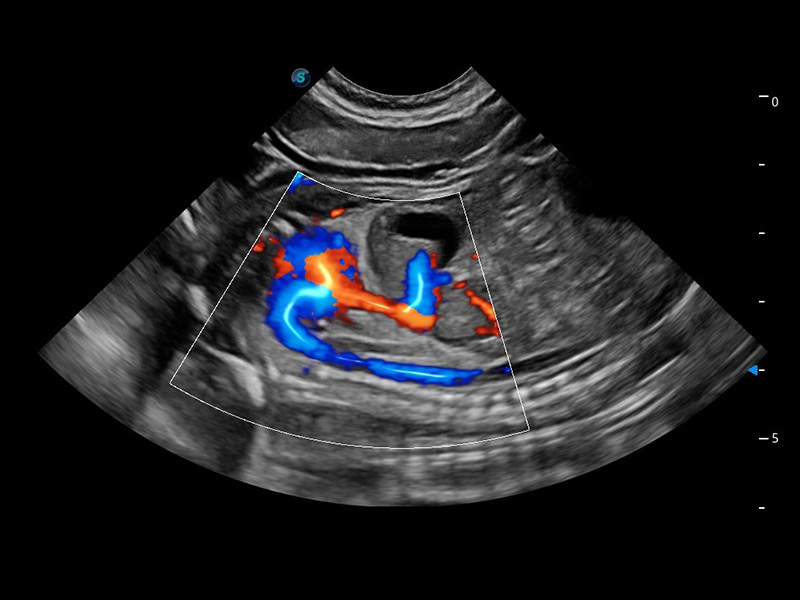

ProPet 60 作为一款高端台式动物超声设备,为动物医生的日常诊断提供了一系列贴合动物临床需求、解决临床实际问题的高级成像功能。凭借全系列高清探头,满足医生对腹部、心脏、生殖、浅表、肌骨等成像的所有需求,切实帮助您提升检查效率,提高诊断信心。

兽用彩色多普勒超声诊断系统